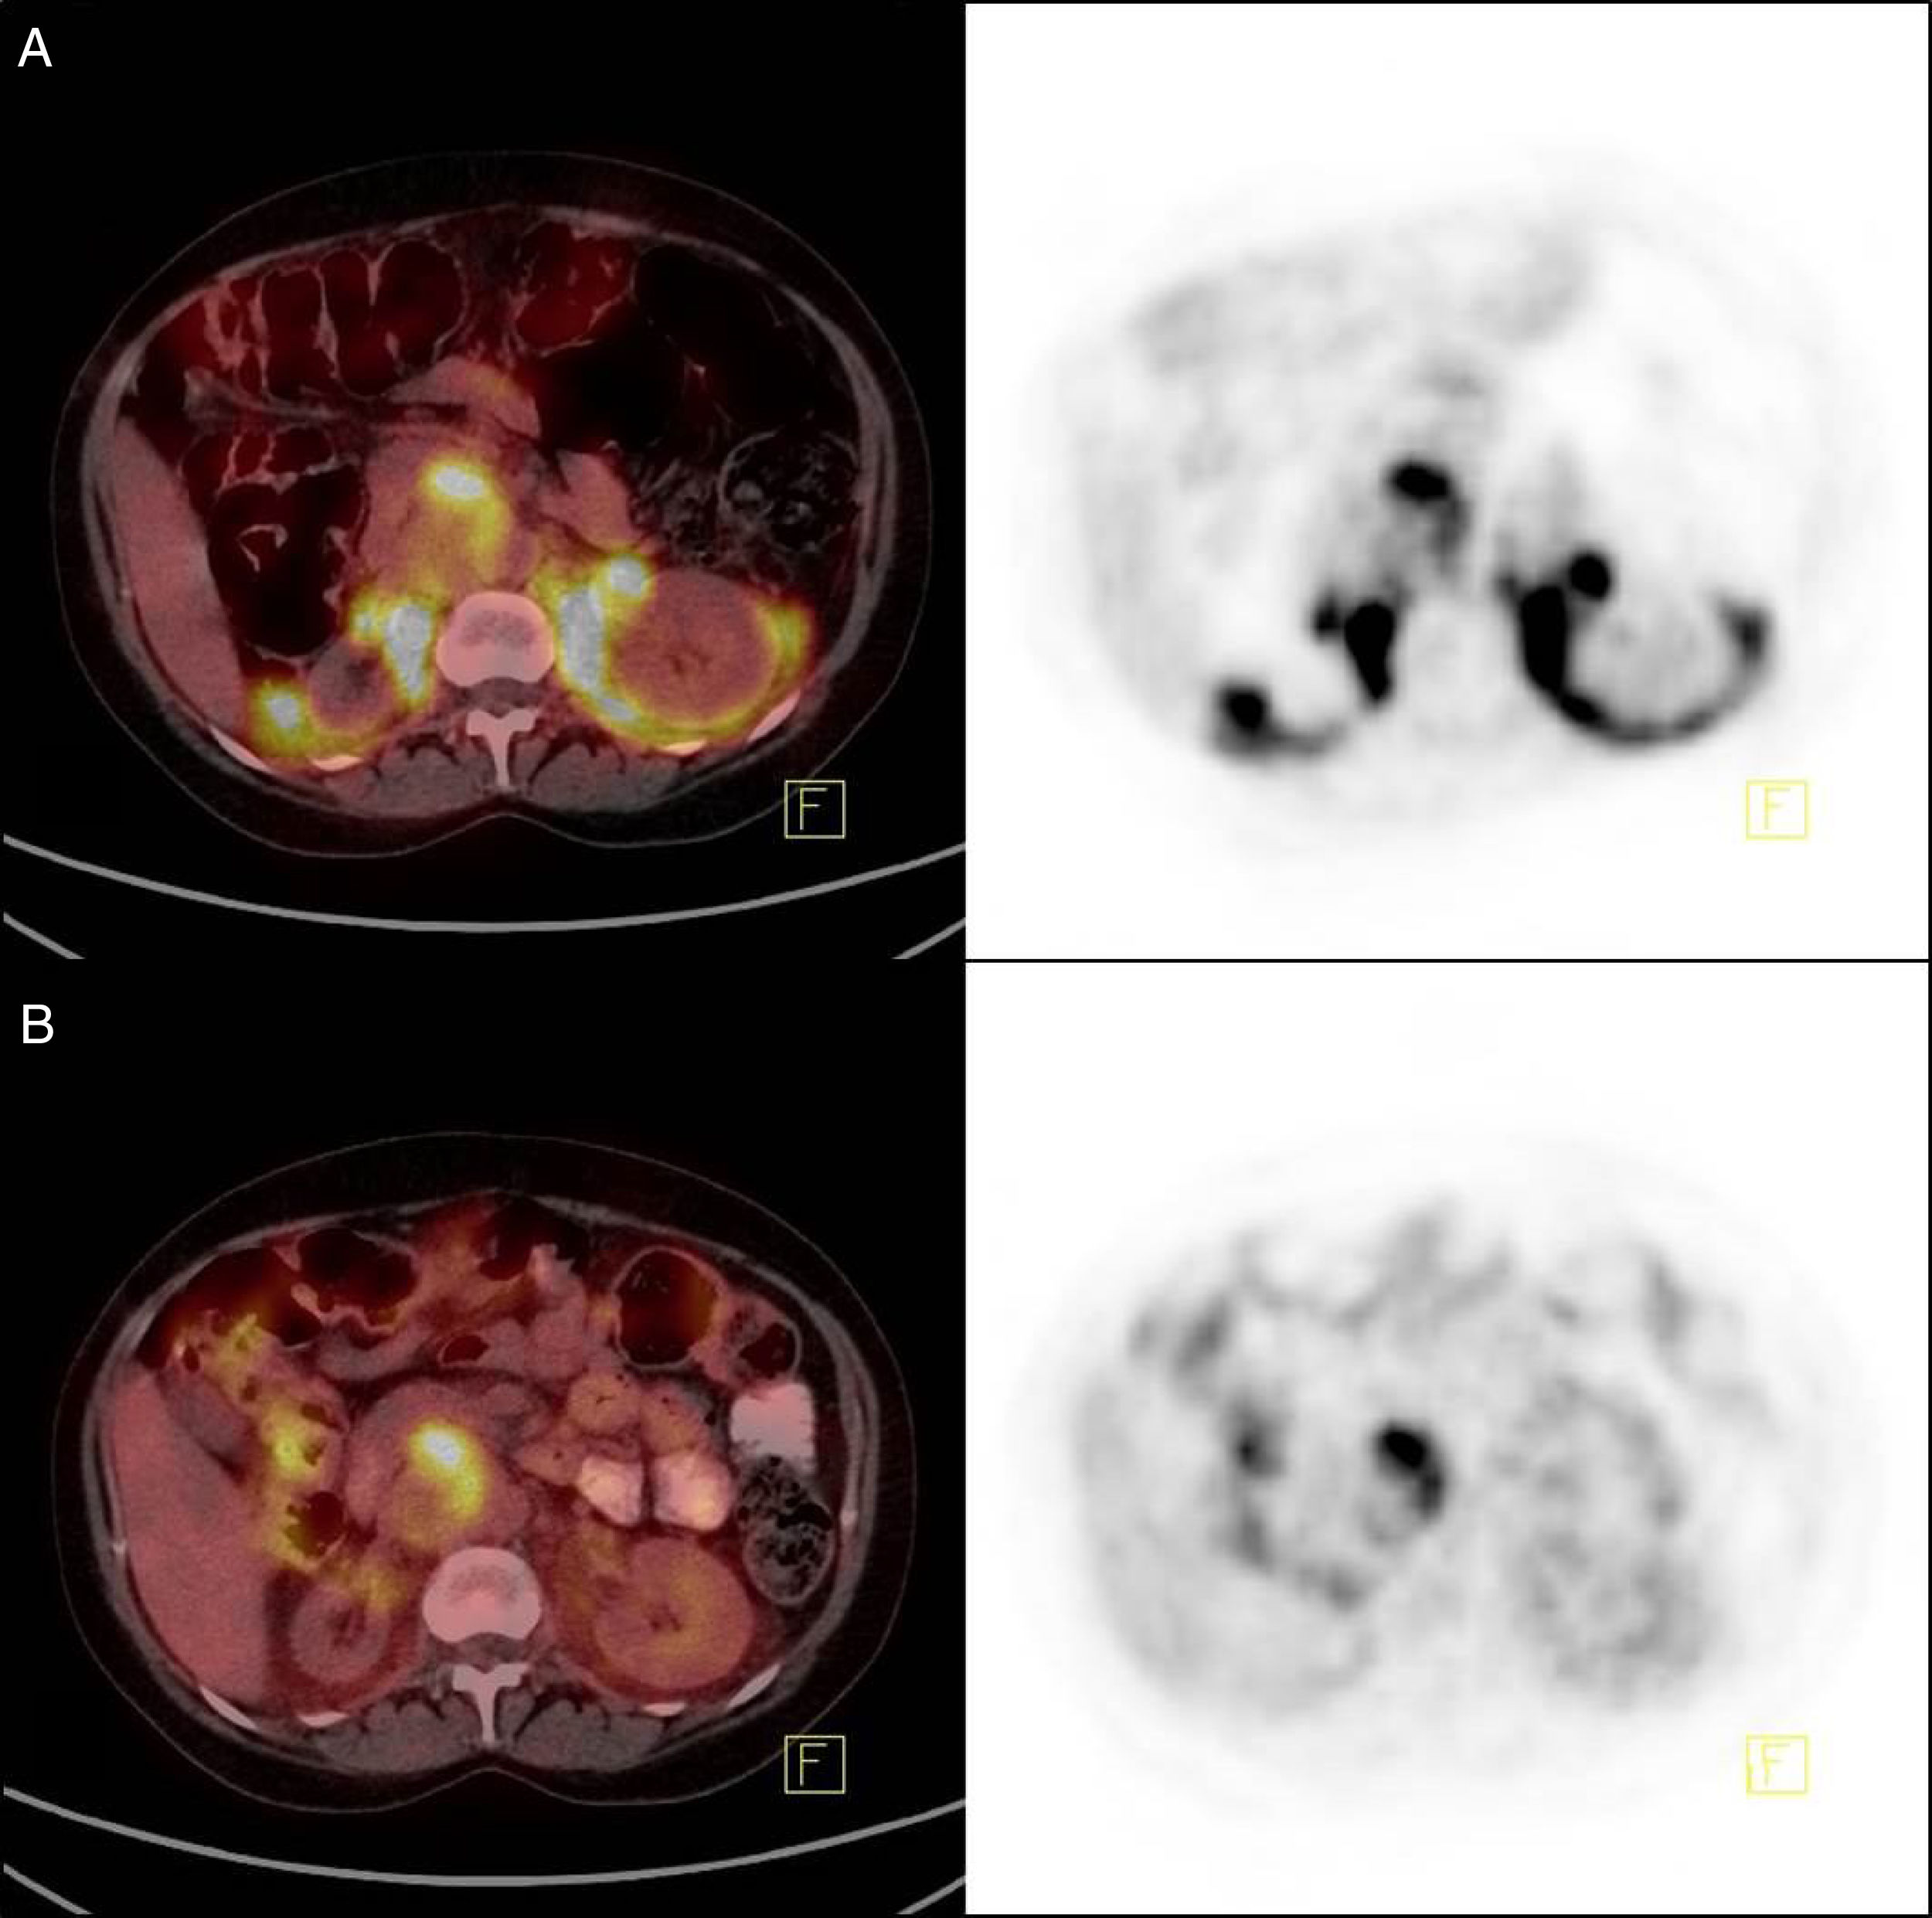

Brown Fat Pet/ct